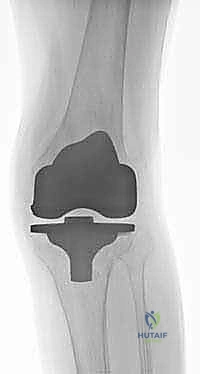

| نوع المفصل المستخدم | مفصل قياسي سطحي. | مفصل مراجعة مع سيقان معدنية (Stems) ودعامات. |

5. السيقان الممتدة (Intramedullary Stems)

في جميع حالات المراجعة تقريباً، لا يمكن الاعتماد فقط على الجزء العلوي من قصبة الساق للتثبيت بسبب ضعف العظم. لذلك، يتم استخدام مفاصل ذات "سيقان" معدنية طويلة تمتد داخل القناة النخاعية لعظم قصبة الساق (Diaphysis). تقوم هذه السيقان بنقل الضغط والوزن من المنطقة الضعيفة في الأعلى إلى العظم القوي في الأسفل، مما يحمي المنطقة المعاد بناؤها ويضمن استقرار المفصل.